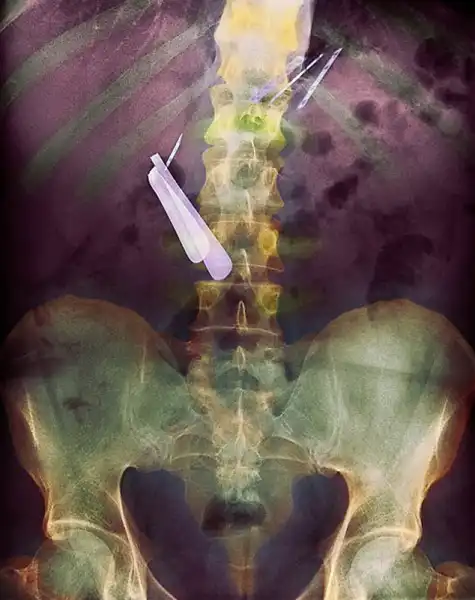

Хирургические ножницы, случайно забытые в теле пациентки после операции. Ножницы были обнаружены лишь через 18 месяцев после операции, т.к. женщина жаловалась на постоянную боль в кишечнике.

Цветной снимок предметов, которые проглотил пациент, и которые застряли в его кишечнике, включая ложку и лезвие.

Цветной рентген желудка пациента, который проглотил бритву (по центру слева) и лезвия (вверху справа).